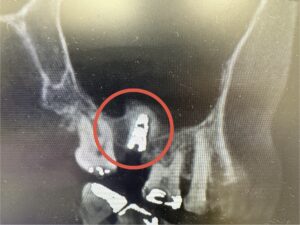

術後写真

ソケットリフト法(元々の骨がない場合に、人工骨をたしていき、インプラントを、埋入するテクニック)

拡大写真